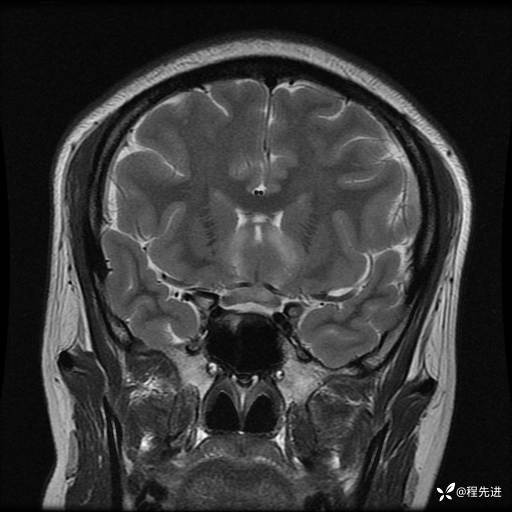

MRI平扫+增强:

T2: